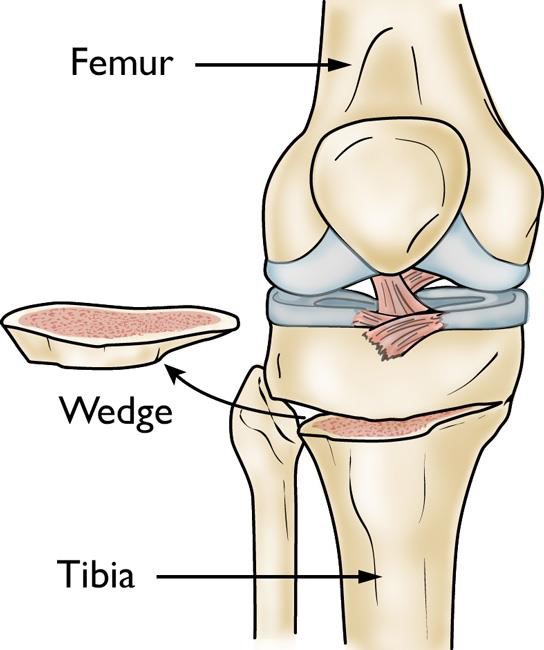

In a tibial osteotomy, a wedge of bone is removed to straighten out the leg.